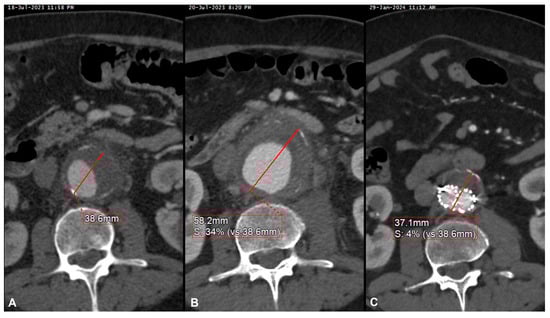

| 9 | M | 69 | Sepsis in pre-existing AAA | Salmonella spp. Non-Typhi | Yes | Symptomatic rapidly growing AAA | Cotrimoxazol | EVAR | Alive | 7 | Increase in wall thickening | - |

| 15 | M | 61 | Endocarditis | Staphylococcus aureus | No | Symptomatic rapidly growing AAA | Oxacyllin | EVAR | Alive | 11 | Shrinkage | - |